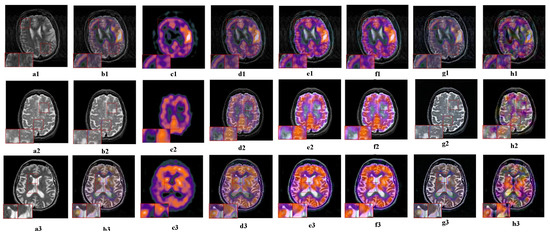

5.2.4. Fusion Analysis on MRI-PET

5.2.5. Fusion Analysis on MR-SPECT